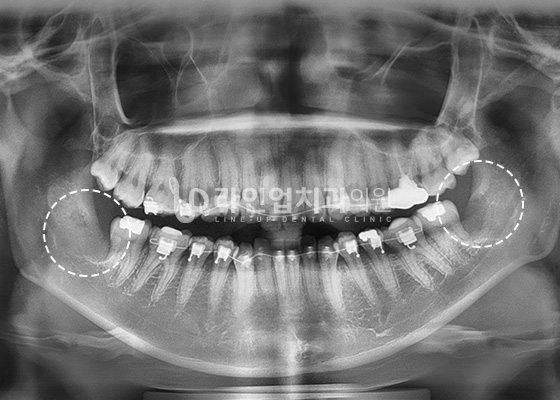

智齿拔除案例

After